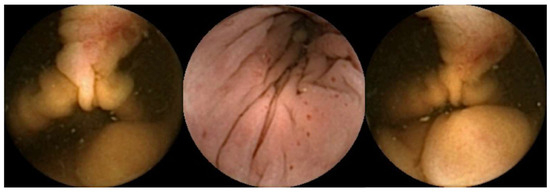

- Majtner, T.; Brodersen, J.B.; Herp, J.; Kjeldsen, J.; Halling, M.L.; Jensen, M.D. A deep learning framework for autonomous detection and classification of Crohn’s disease lesions in the small bowel and colon with capsule endoscopy. Endosc. Int. Open 2021, 9, E1361–E1370. [Google Scholar] [CrossRef]

- Ferreira, J.P.S.; de Mascarenhas Saraiva, M.; Afonso, J.P.L.; Ribeiro, T.F.C.; Cardoso, H.M.C.; Ribeiro Andrade, A.P.; de Mascarenhas Saraiva, M.N.G.; Parente, M.P.L.; Natal Jorge, R.; Lopes, S.I.O.; et al. Identification of Ulcers and Erosions by the Novel Pillcam™ Crohn’s Capsule Using a Convolutional Neural Network: A Multicentre Pilot Study. J. Crohns Colitis 2022, 16, 169–172. [Google Scholar] [CrossRef] [PubMed]

- Ribeiro, T.; Mascarenhas, M.; Afonso, J.; Cardoso, H.; Andrade, P.; Lopes, S.; Ferreira, J.; Mascarenhas Saraiva, M.; Macedo, G. Artificial intelligence and colon capsule endoscopy: Automatic detection of ulcers and erosions using a convolutional neural network. J. Gastroenterol. Hepatol. 2022, 37, 2282–2288. [Google Scholar] [CrossRef] [PubMed]